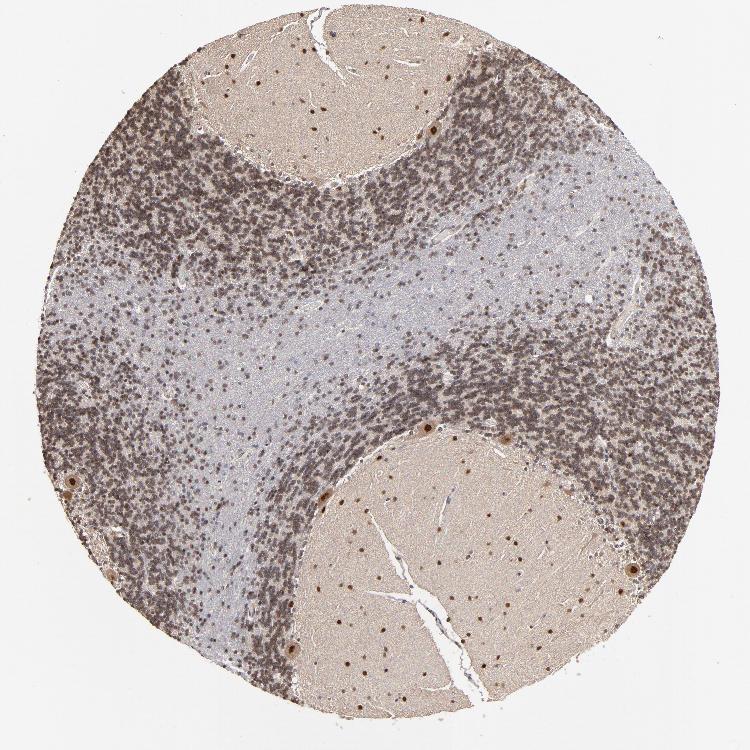

BRAIN CEREBELLUM Show tissue menu

CEREBELLUM - Expression summary

Cells in granular layer: Medium

Cells in molecular layer: Low

Purkinje cells: Low

CEREBELLUM - Antibody stainingi

Antibody staining in the annotated cell types in the current human tissue is reported as not detected, low, medium, or high, based on conventional immunohistochemistry profiling in selected tissues. This score is based on the combination of the staining intensity and fraction of stained cells.

Each image is clickable and will lead to virtual microscopy that enables deeper exploration of all samples and also displays staining intensity scores, fraction scores and subcellular localization as well as patient and tissue information for each sample.

Antibody HPA002548Antibody CAB022718

Purkinje cells HighHigh

Cells in granular layer MediumMedium

Cells in molecular layer MediumMedium